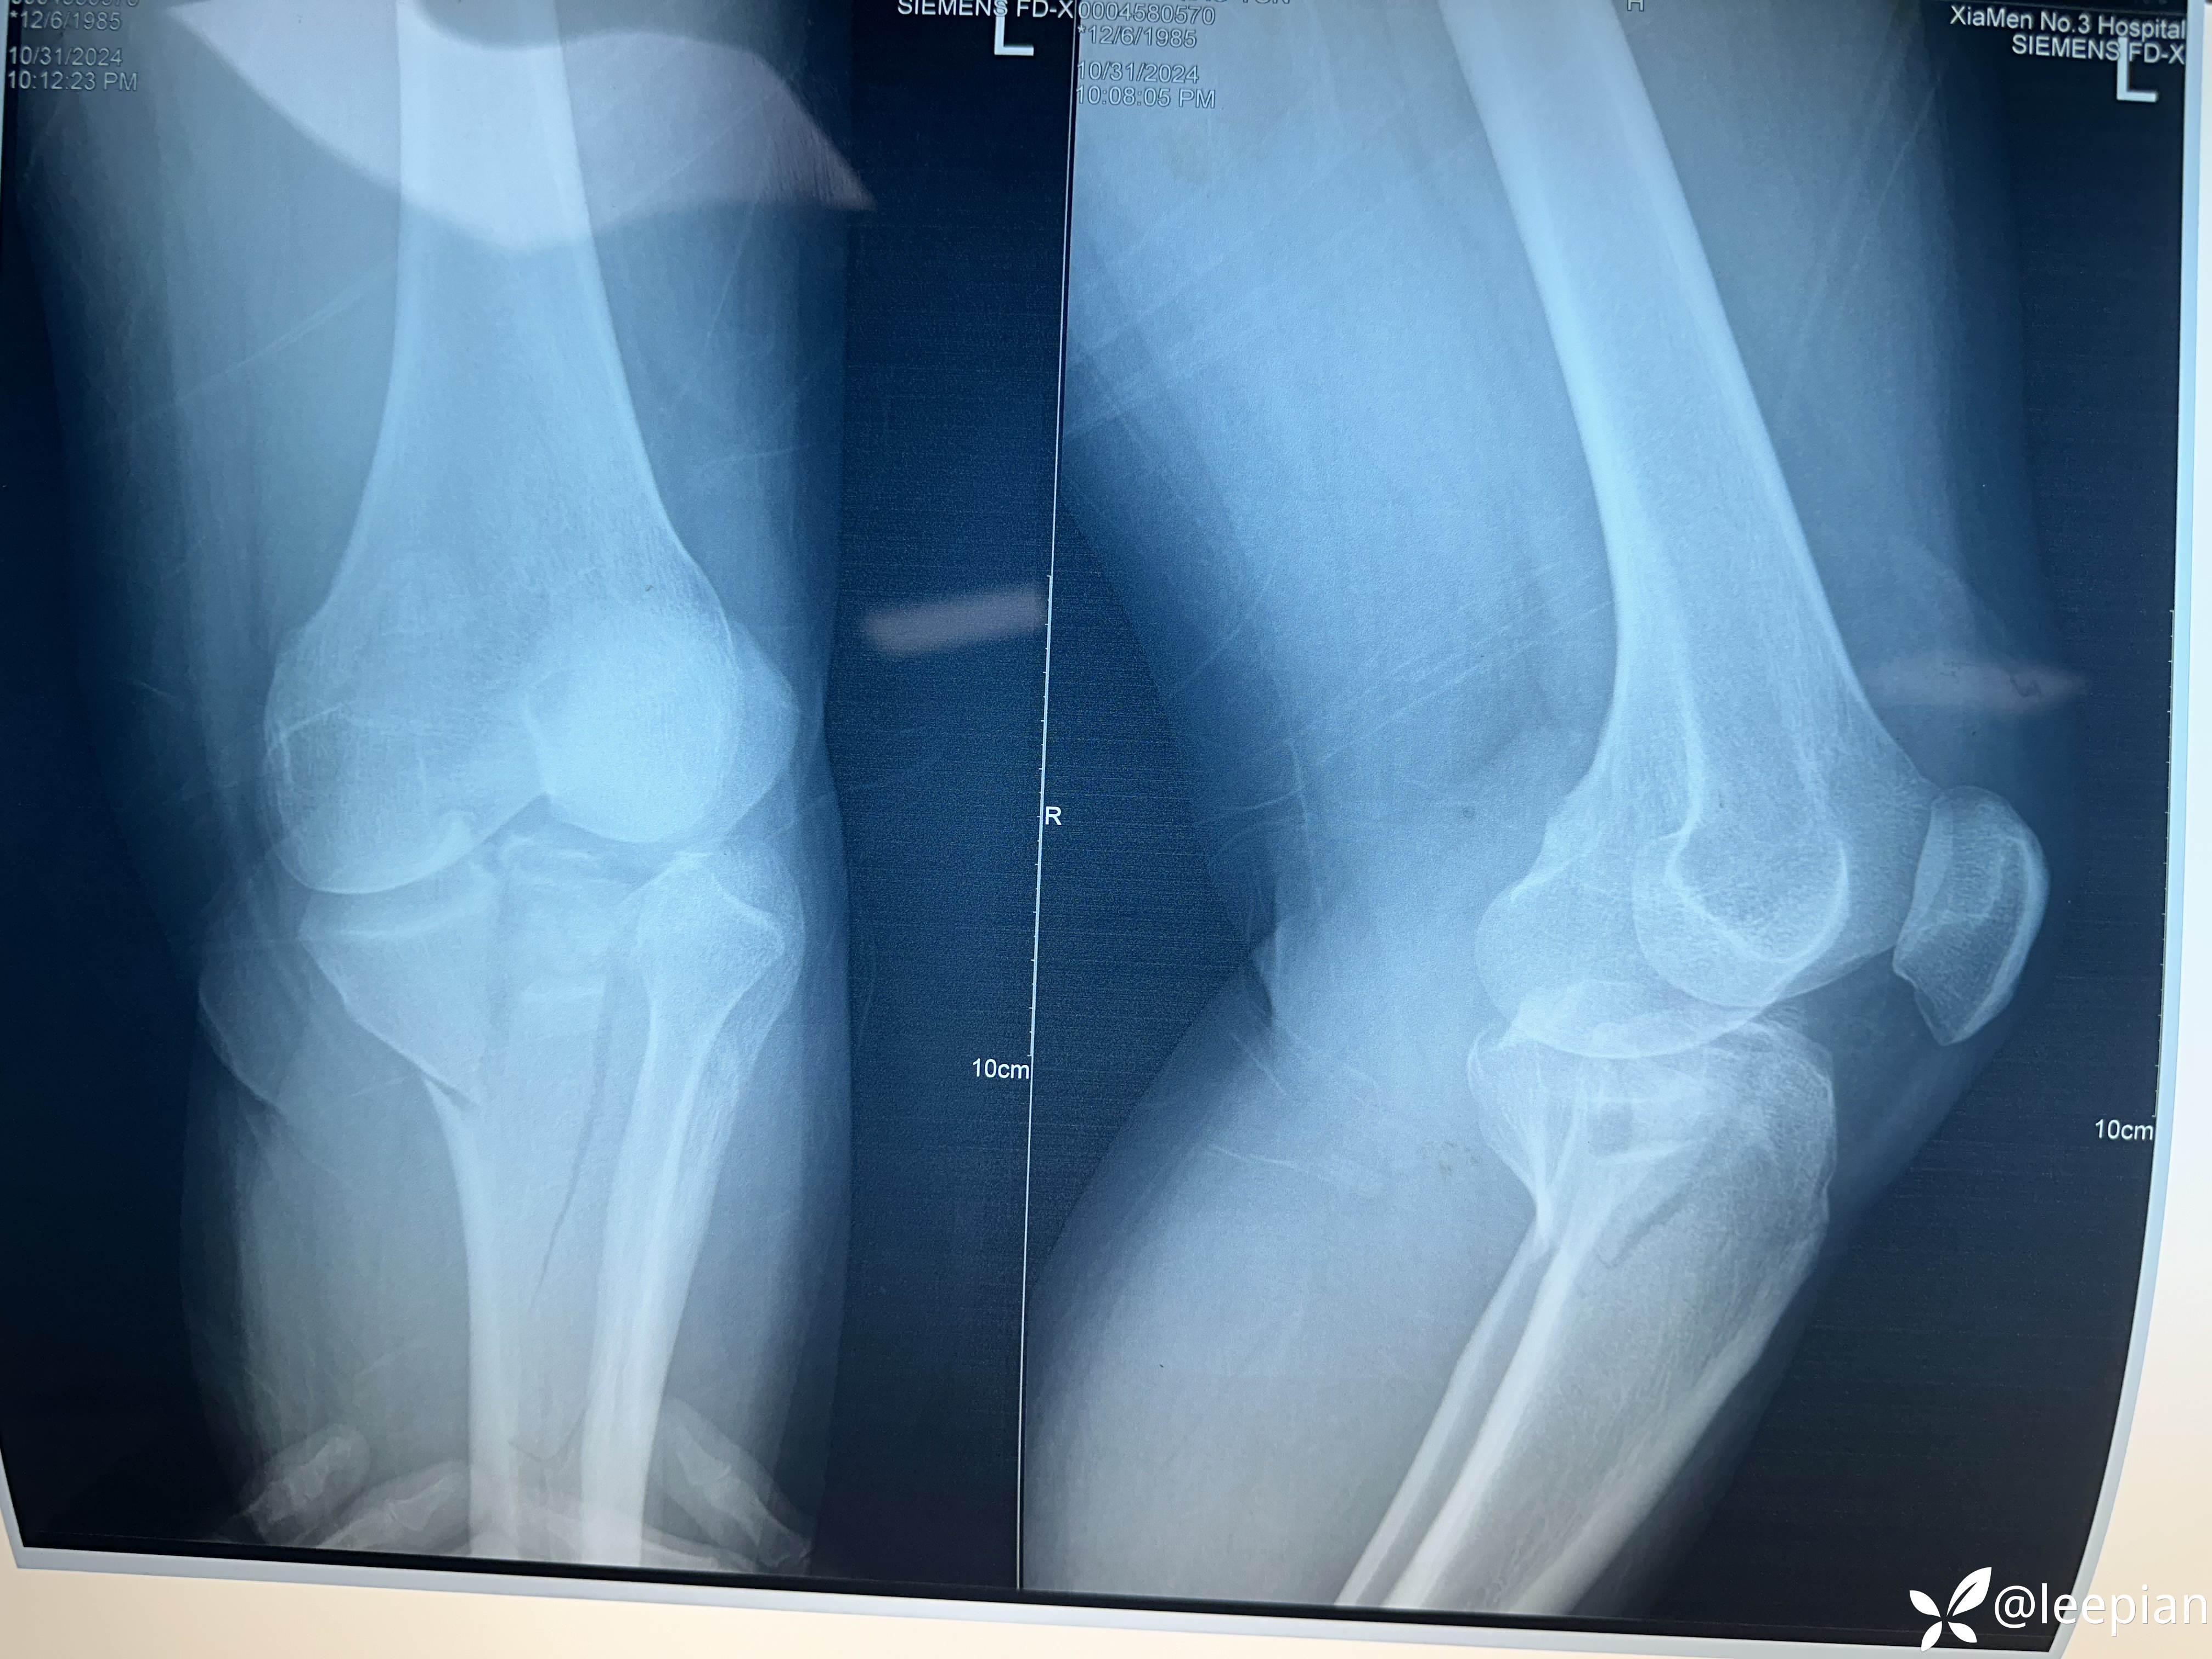

【检查】:

【临床诊断】:胫骨平台骨折脱位